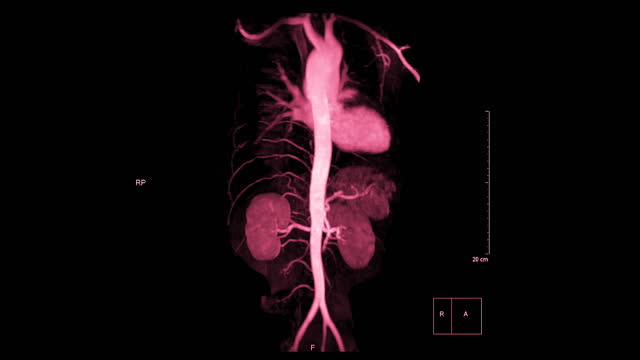

신장암은 흡연, 비만, 고혈압 등과 관련된 원인이 있을 수 있습니다. 그러나 암의 발생 원인을 규명하는 것보다 더 중요한 것은 조기 발견입니다. 신장암은 양쪽 신장에서 동시에 발견되는 경우가 드물며 대부분 한쪽에서 발견됩니다.

신장암은 혈액 검사나 소변 검사로는 조기 진단하기 어렵습니다. 따라서 건강을 유지하고자 하는 목적으로는 초음파 검사를 적어도 일 년에 한 번 받는 것이 좋습니다. 초음파 검사를 통해 작은 크기의 신장암도 조기에 발견할 수 있습니다.